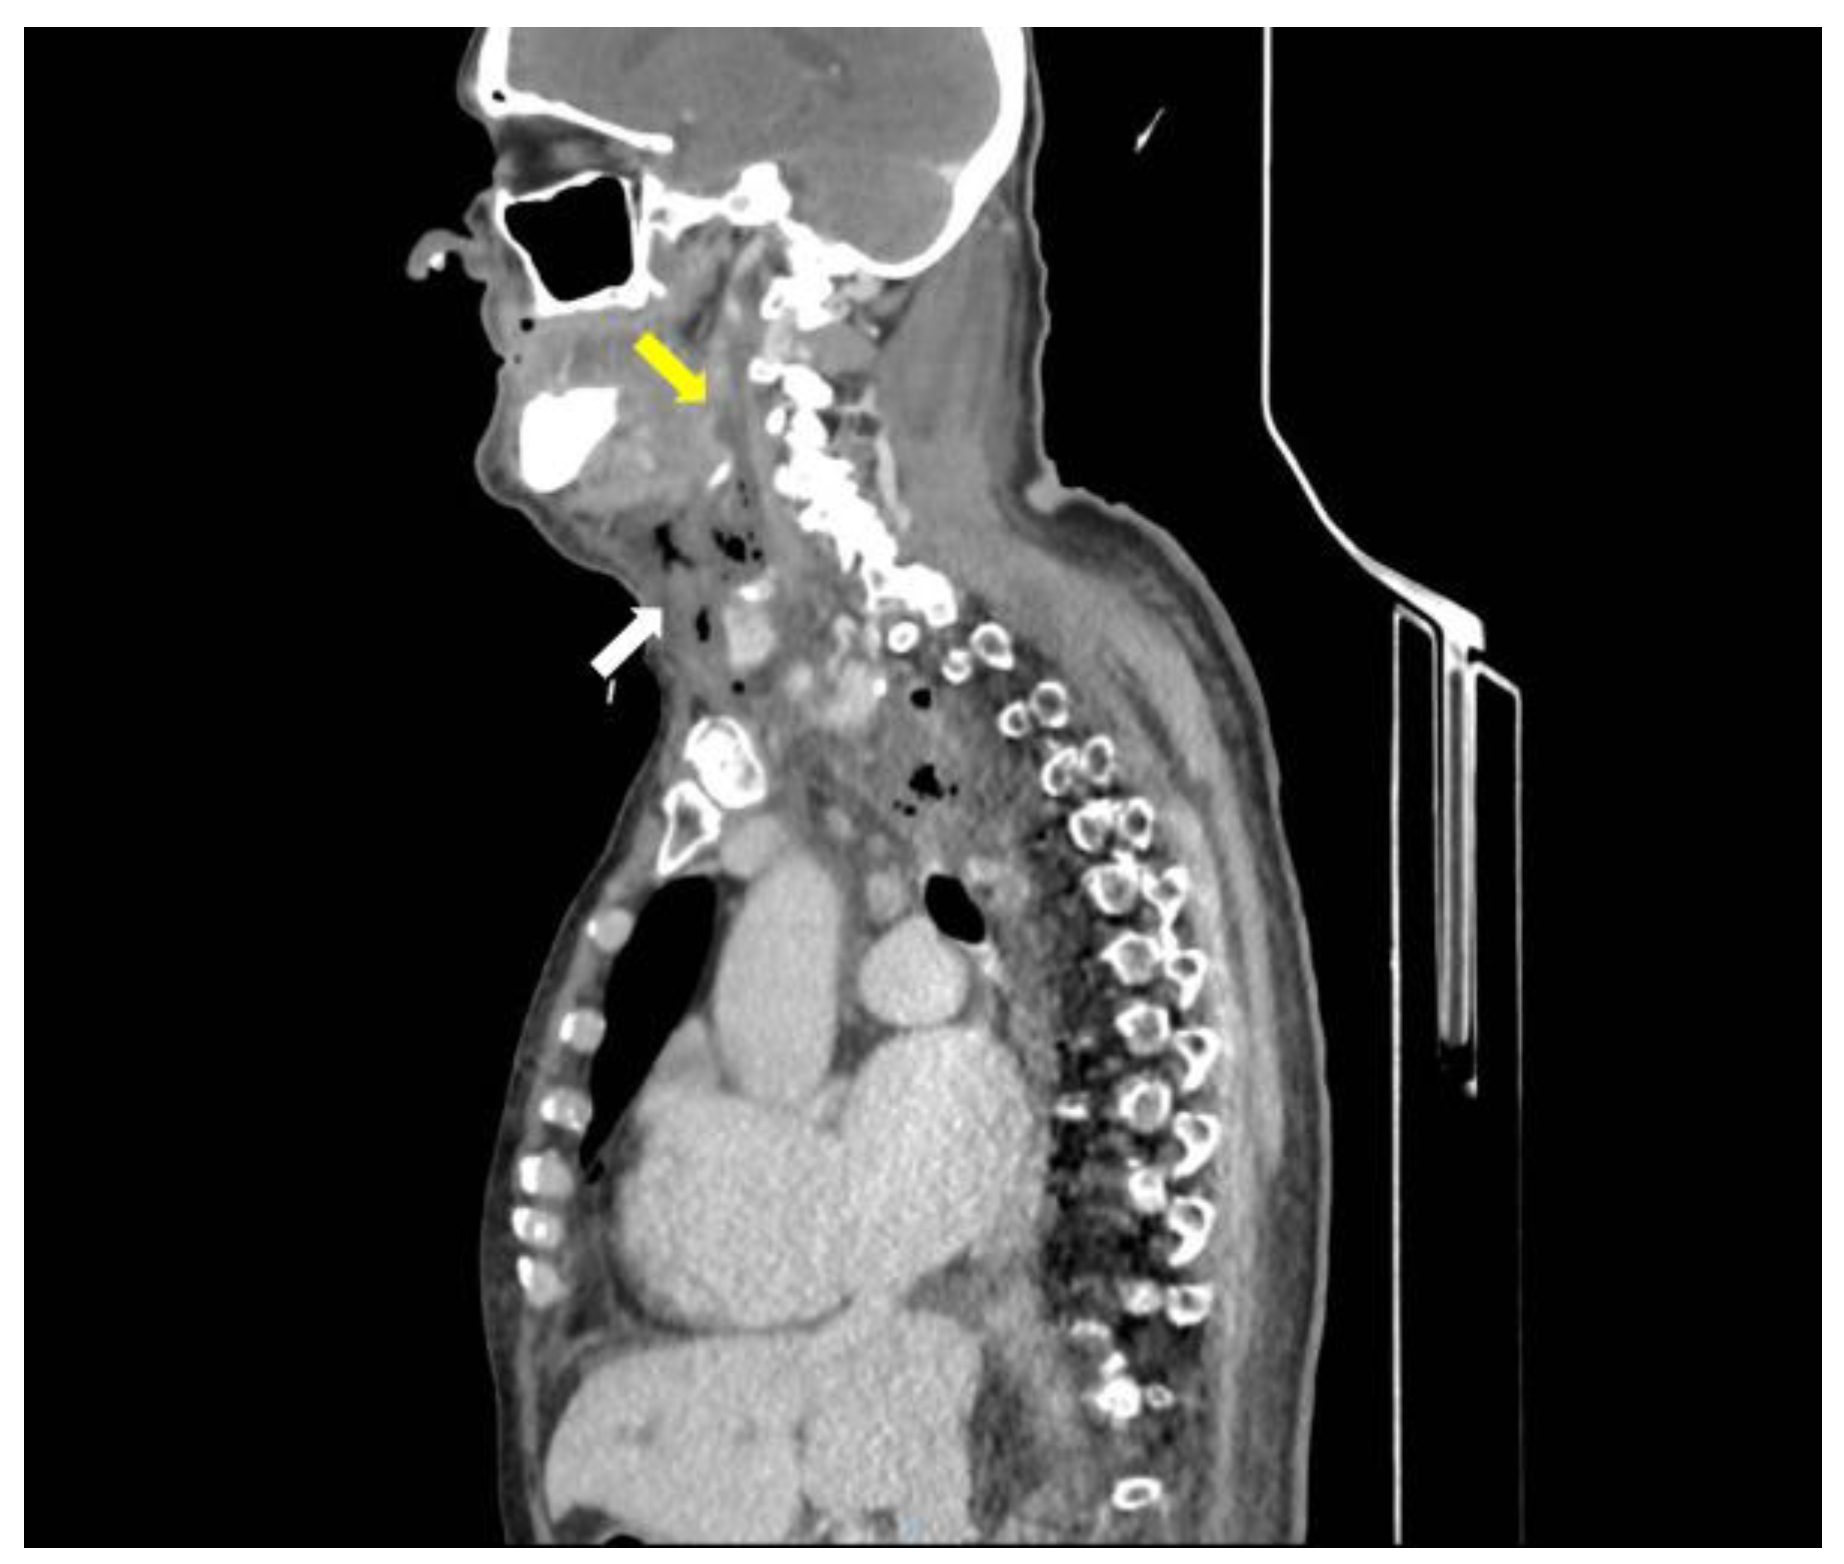

A CT scan of the head, neck, and chest with intravenous contrast, revealed a retrotonsillar fluid collection, with a maximum diameter of 10 cm, extended anteriorly to the right lobe of the thyroid gland (Figure 1). Air bubbles and minimal fluid were present from the right submandibular area to the lower mediastinum between the spine, the descending thoracic aorta, and the trachea (Figure 2).

Figure 1.

CT scan of head, neck, and chest with intravenous contrast material, shows a retropharyngeal collection (yellow arrow) and submandibular air bubbles (white arrow).